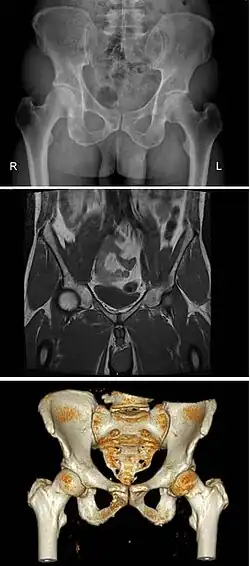

The principal differences between male and female true and false pelvis include:

- The female pelvis is larger and broader than the male pelvis which is taller, narrower, and more compact.[10] The female pelvis is lighter and thinner than the male pelvis.[11]

- The female inlet is larger and oval in shape, while the male sacral promontory projects further (i.e. the male inlet is more heart-shaped).[10]

- The sides of the male pelvis converge from the inlet to the outlet, whereas the sides of the female pelvis are wider apart.[12]

- The angle between the inferior pubic rami is acute (70 degrees) in males, but obtuse (90–100 degrees) in females. Accordingly, the angle is called subpubic angle in males and pubic arch in females.[10] Additionally, the bones forming the angle/arch are more concave in females but straight in males.[13]

- The distance between the ischia bones is small in males, making the outlet narrow, but large in females, who have a relatively large outlet. The ischial spines and tuberosities are heavier and project farther into the pelvic cavity in males. The greater sciatic notch is wider in females.[13]

- The iliac crests are higher and more pronounced in males, making the male false pelvis deeper and more narrow than in females.[13]

- The male sacrum is long, narrow, more straight, and has a pronounced sacral promontory. The female sacrum is shorter, wider, more curved posteriorly, and has a less pronounced promontory.[13]

- The acetabula are wider apart in females than in males.[13] In males, the acetabulum faces more laterally, while it faces more anteriorly in females. Consequently, when males walk the leg can move forwards and backwards in a single plane. In females, the leg must swing forward and inward, from where the pivoting head of the femur moves the leg back in another plane. This change in the angle of the femoral head gives the female gait its characteristic (i.e. swinging of hips).[14]